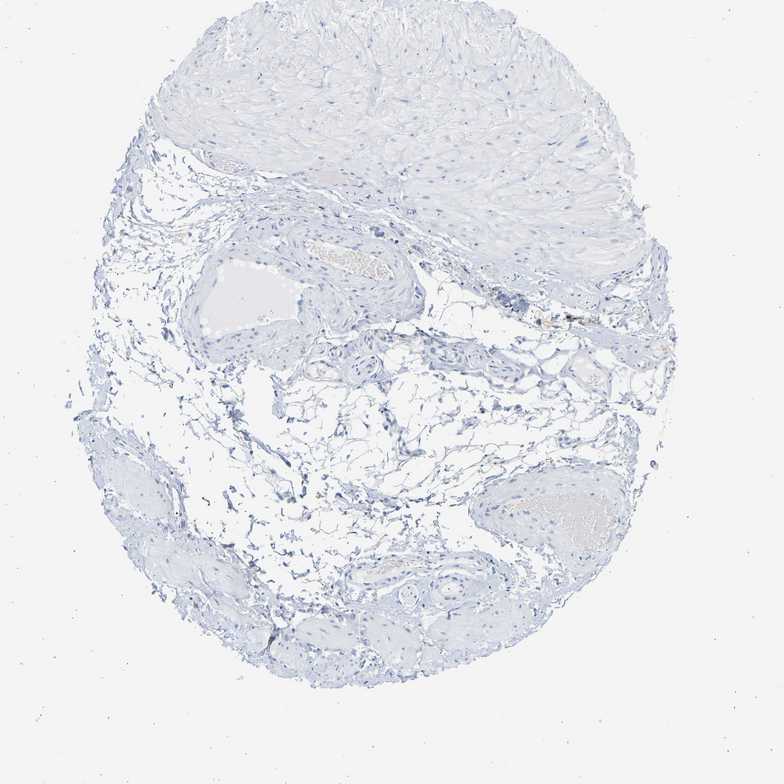

SOFT TISSUE 2 - Antibody stainingi

Antibody staining in the annotated cell types in the current human tissue is reported as not detected, low, medium, or high, based on conventional immunohistochemistry profiling in selected tissues. This score is based on the combination of the staining intensity and fraction of stained cells.

Each image is clickable and will lead to virtual microscopy that enables deeper exploration of all samples and also displays staining intensity scores, fraction scores and subcellular localization as well as patient and tissue information for each sample.

Antibody HPA026813Antibody CAB020824

Fibroblasts Not detectedNot detected

Peripheral nerve Not detectedNot detected